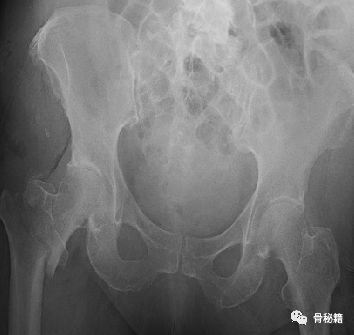

这样一个粗隆间骨折,骨折线经过入钉点,这个时候复位比较困难,及时复位,进钉的时候也很容易将骨折线撑开而造成复位不良。